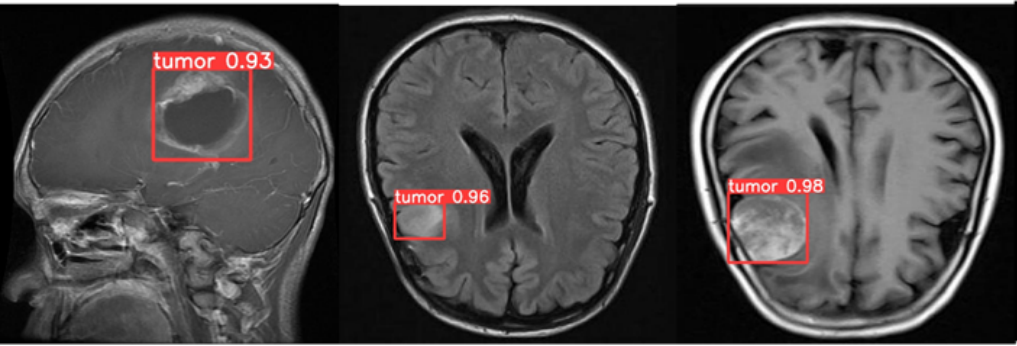

- Solution: Implemented a multi-stage pipeline using augmentation → baseline CNN → transfer learning (EfficientNetB4) → tumor-region visualization. This ensured robustness while keeping the model lightweight and stable.

- Result: Achieved ~0.97 validation F1-score and smooth loss convergence. Transfer learning significantly outperformed models trained from scratch.

To achieve higher performance and generalization, we adopted EfficientNetB4 pre-trained on ImageNet and fine-tuned it for binary tumor classification. Transfer learning helped retain low-level features like gradients and textures while adapting high-level layers to MRI patterns.

This approach reduced training time, stabilized gradients, and consistently outperformed custom CNN results. Below are the updated final results using Transfer Learning.

- Transfer learning (EfficientNetB4) achieved ~0.97 F1, outperforming CNN-from-scratch by a significant margin.